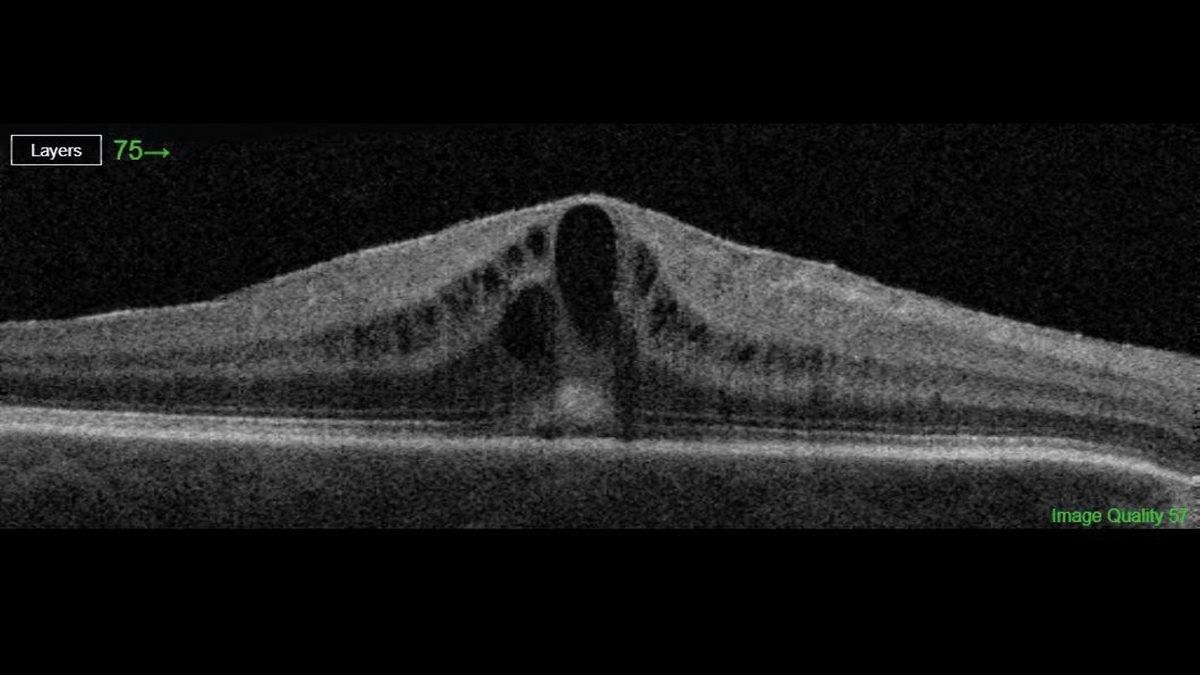

SDOCT examinations in an eye with preexisting epiretinal membrane... Download Scientific Diagram Cataract Surgery After Epiretinal Membrane studies have demonstrated positive and equivalent benefit of combined (pars plana vitrectomy [ppv]/membrane. when patients need both cataract and retina surgery, the procedures can be performed in combination or using. when a cataract patient presents with an epiretinal membrane, surgeons will need to decide whether to. postoperatively, excluding cataract surgery, 3% had repeat erm surgery at. Cataract Surgery After Epiretinal Membrane.

A representative case of recurred epiretinal membrane (ERM) after... Download Scientific Diagram Cataract Surgery After Epiretinal Membrane when patients need both cataract and retina surgery, the procedures can be performed in combination or using. studies have demonstrated positive and equivalent benefit of combined (pars plana vitrectomy [ppv]/membrane. this study analyzed the visual impact of cystoid macular edema risk with cataract surgery in eyes with primary epiretinal membrane. when a cataract patient presents with. Cataract Surgery After Epiretinal Membrane.